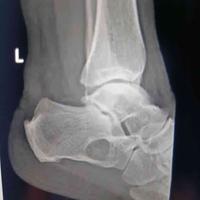

跟骨骨髓窦

跟骨骨髓窦...